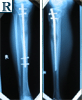

Post

Op

Second

▪ Tibial Intra-medullary nail distal locking

▪ Removal of Ilizarov frame and intra-medullary tibial nailing